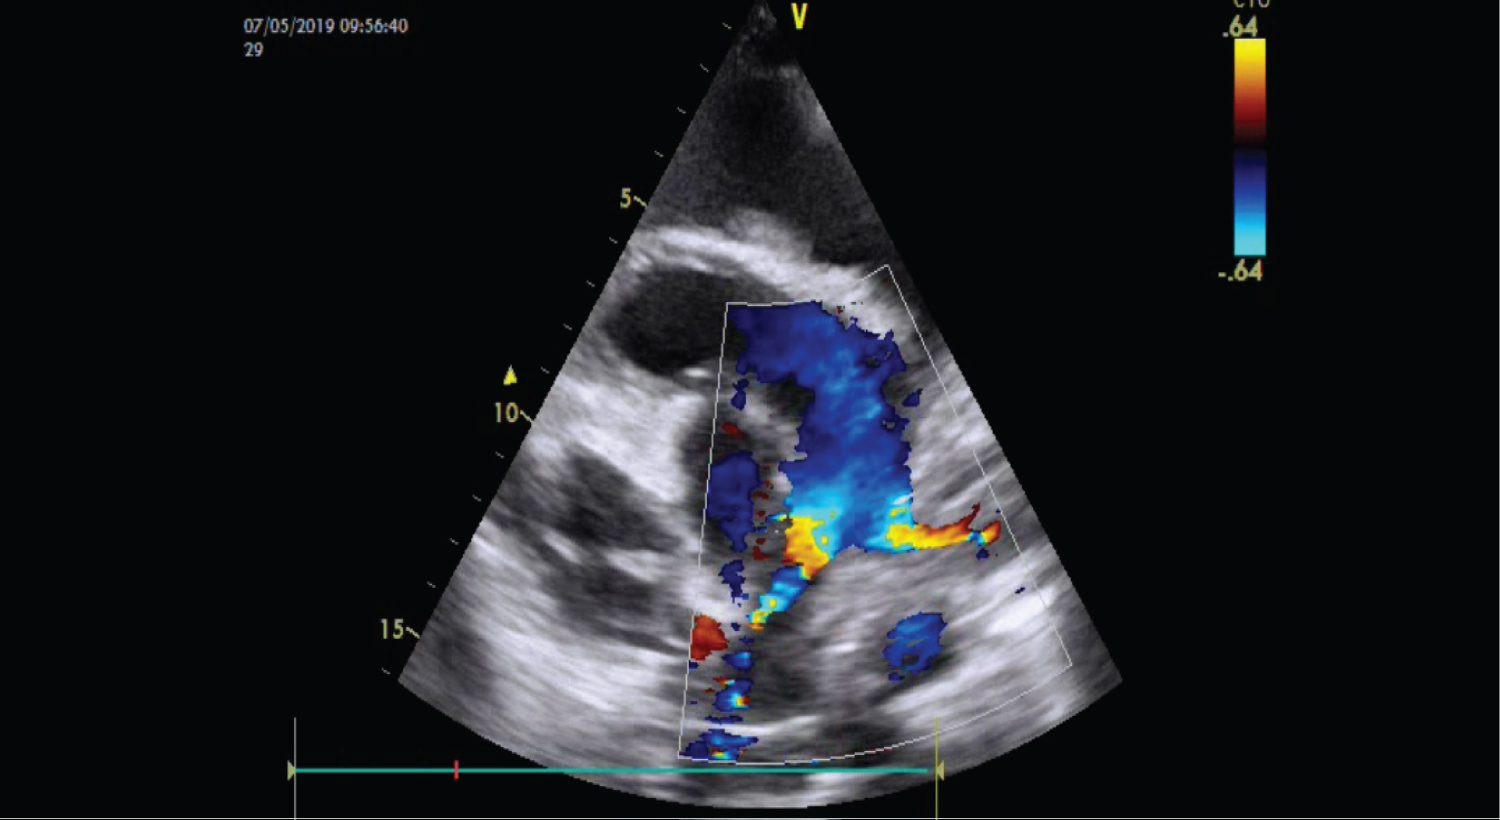

26-year-old lady admitted with shortness of breath and chest discomfort for last one and half months. She had no history of chest pain. She was not suffering from any major illness neither she was taking any medications on regular basis. On initial examination there was pallor and bipedal oedema. SpO2 was 94% in room air. Cardiovascular examinations reveal short systolic murmur in the pulmonary area with no radiation and continuous murmurs in left axillary area of same intensity. Chest examinations revealed normal vesicular breath sound in both lung fields. Electrocardiogram (ECG) revealed sinus tachycardia with heart rate of 116/min, regular in rhythm. Chest Xray was advised which revealed no significant abnormalities. Echocardiogram was advised which revealed normal Left Ventricular systolic function with normal chambers dimension and function. There was no significant valvular abnormality. Main pulmonary artery was normal in calibre. Left and Right Pulmonary artery was found to be stenosed (Figure 1 and Figure 2). It was long segment stenosis which was clearly visible in echocardiogram images and Video 1. Doppler examinations revealed pressure gradient of 22 mm of Hg and 31 mm of Hg in left and right pulmonary artery branch respectively. Complete Blood Count and other relevant laboratory investigations were also sent during admission and it revealed that total leukocyte count was 2 lakhs/cmm with numerous atypical blood cell (myelocytes, metamyelocyte, promyelocyte) including blast cell. She was diagnosed to have been suffering from Chronic Myeloid Leukaemia (CML). She was referred to Haematology department for further management. She was counselled properly for various approaches to BPAS (balloon plasty, stenting, surgical repair) and was advised to attend cardiology clinic after remission of CML for further treatment of BPAS.

Figure 1: Showing the long stenosed segment of both pulmonary artery branches.

Figure 2: Showing normal pulmonary trunk and stenosed both branches.